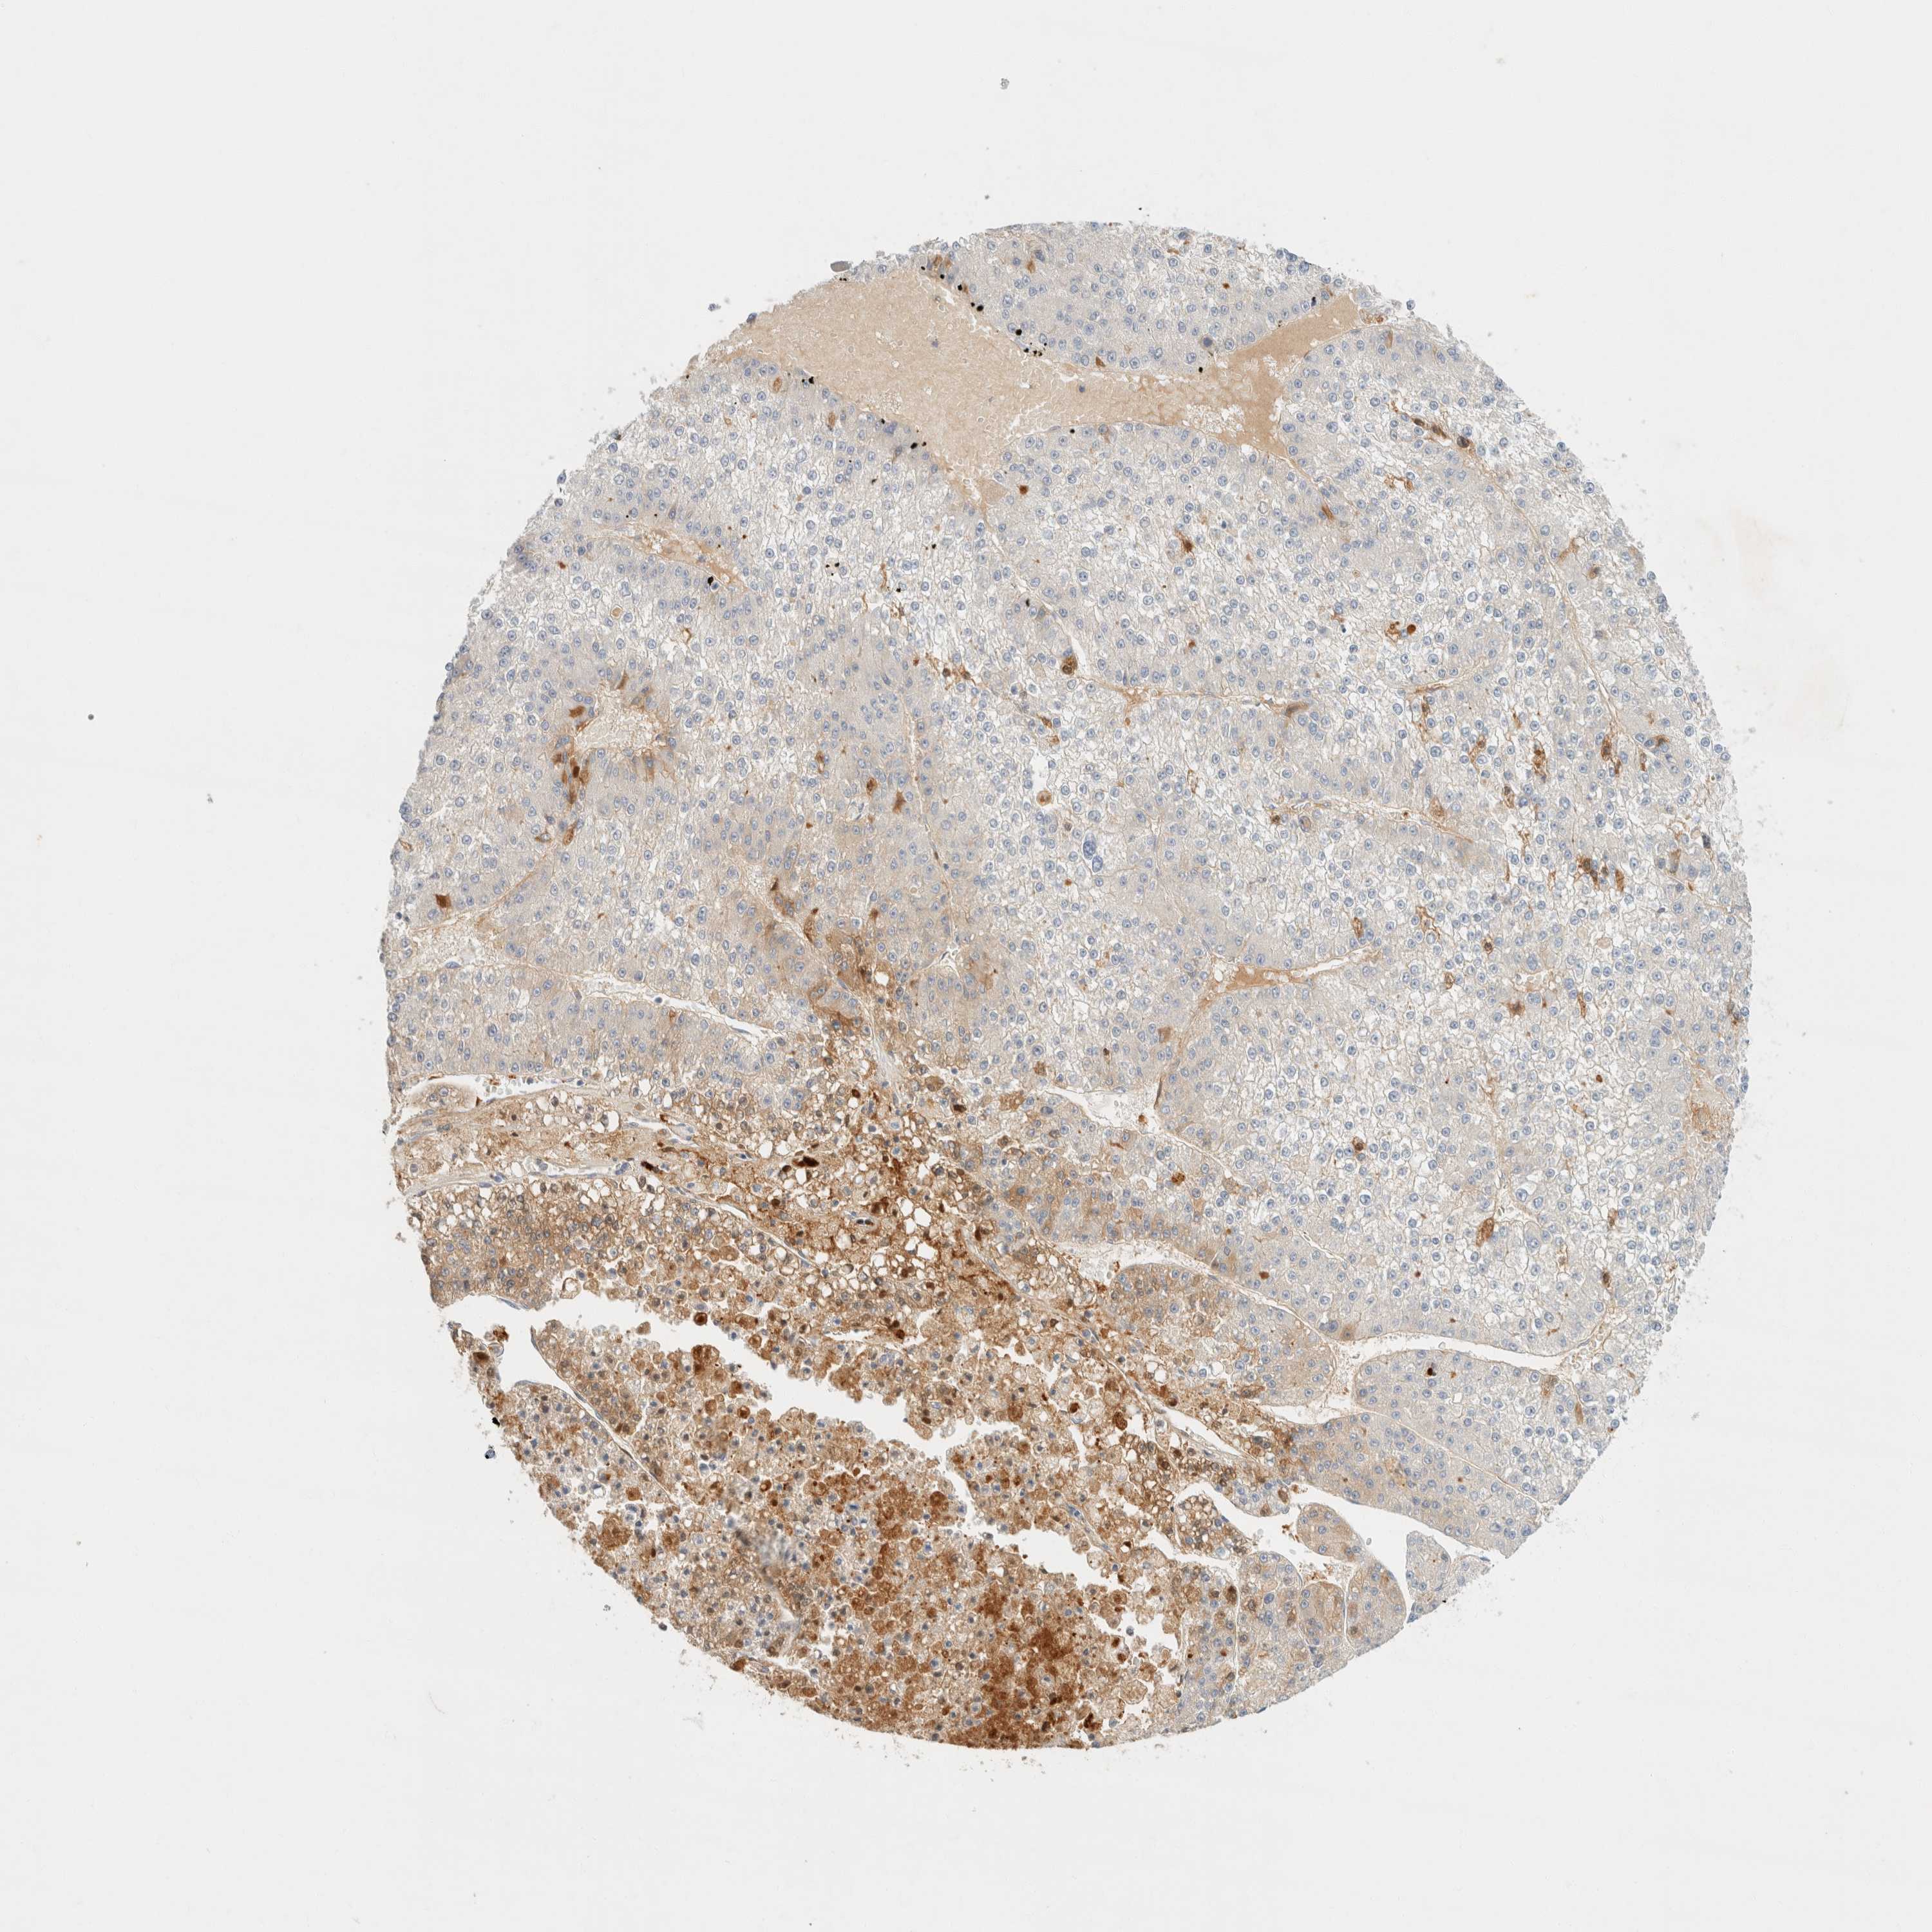

LIVER CANCER - Protein expressioni

A mouse-over function shows sample information and annotation data. Click on an image to view it in a full screen mode. Samples can be filtered based on level of antibody staining by selecting one or several of the following categories: high, medium, low and not detected. The assay and annotation is described here.

Note that samples used for immunohistochemistry by the Human Protein Atlas do not correspond to samples in the TCGA dataset.

Antibody stainingi

Antibody staining in the annotated cell types in the current human tissue is reported as not detected, low, medium, or high, based on conventional immunohistochemistry profiling in selected tissues. This score is based on the combination of the staining intensity and fraction of stained cells.

Each image is clickable and will lead to virtual microscopy that enables deeper exploration of all samples and also displays staining intensity scores, fraction scores and subcellular localization as well as patient and tissue information for each sample.

Antibody HPA023694

Staining

High

Medium

Low

Not detected

Intensity

Strong

Moderate

Weak

Negative

Quantity

>75%

75%-25%

<25%

None

Location

Nuclear

Cytoplasmic/membranous

Cytoplasmic/membranous,nuclear

Cholangiocarcinoma

Carcinoma, Hepatocellular, NOS